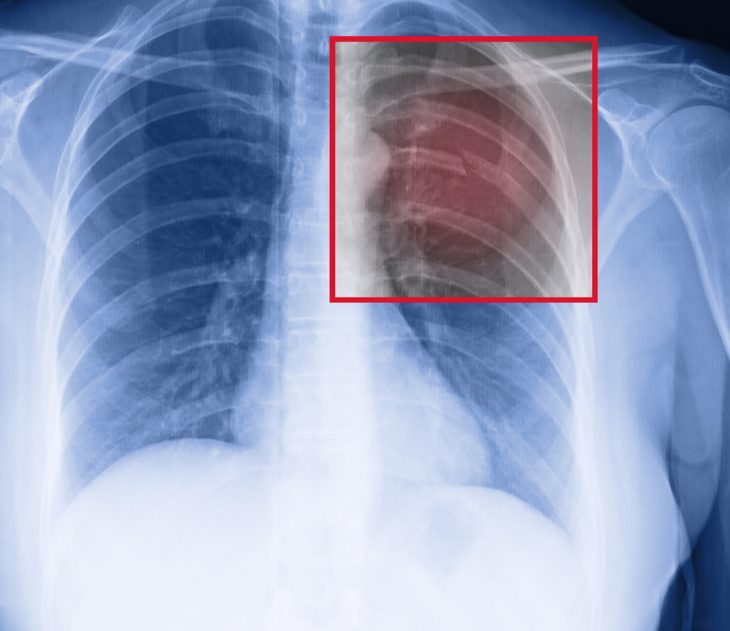

Поврежденные ребра достаточно чувствительны, боль длится несколько недель. Врач может обнаружить наличие деформации при пальпации грудной клетки. Изменения цвета кожи, кровоподтеки указывают на место воздействия травмирующей силы. С целью уточнения диагноза при клинически значимой травме для обнаружения переломов со смещением обычно проводят рентгенографическое обследование.

Так как определить переломы на рентгенограммах не всегда удается, могут быть проведены специфические исследования визуализации ребер. Наиболее информативным методом в этой области считается компьютерная томография. Обычно в диагностике ориентируются на клиническую картину.

- рентгеновские снимки (в переднезадней проекции);

- КТ;

- УЗИ грудной клетки.